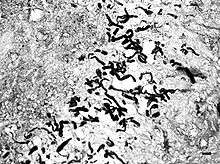

Pythiosis is suspected to be heavily underdiagnosed due to unfamiliarity with the disease, the rapid progression and morbidity, and the difficulty in making a diagnosis. Symptoms often appear once the disease has progressed to the point where treatment are less effective. As the organism is neither a bacterium, virus, nor fungus, routine tests often fail to diagnose it. In cytology and histology, the organism does not stain using Geisma, H&E, or Diff-Quick. GMS staining is required to identify the hyphae in slides. Additionally, the symptoms are usually nonspecific and the disease is not normally included in a differential diagnosis.